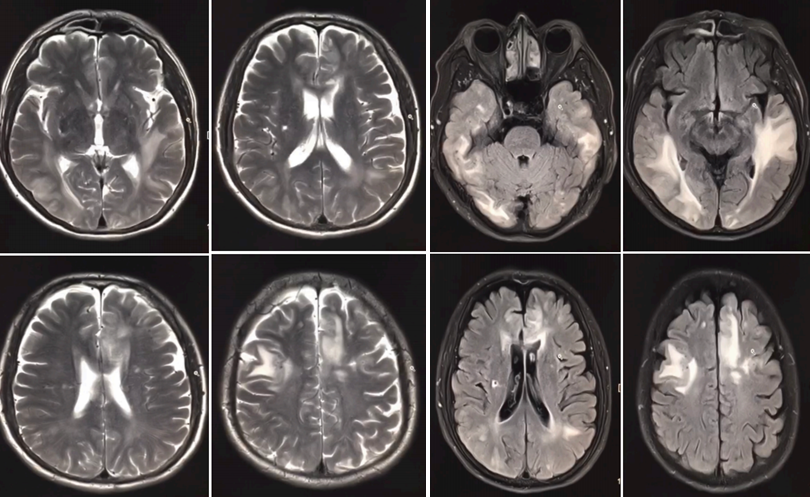

病例6

患者女,31岁,3年前出现听力下降,间断抽搐。

答案:线粒体脑肌病伴高乳酸血症和卒中样发作综合征(MELAS)。临床表现为多系统受累,主要累及中枢神经系统、肌肉、听神经、胰腺、心脏以及肾脏等;卒中样发作,癫痫是最常见的临床表现,其次为肌无力、头痛、智能发育迟缓以及身材矮小。影像学特点:病灶好发于皮质及皮质下白质区,深部白质较少受累。可单发或多发,多为不对称分布,与脑动脉供血区不一致,且呈多变性、游走性;增强扫描病灶不强化或轻度强化,或为沿病变区脑回分布的线样强化;常伴基底节钙化,主要位于苍白球,其次是丘脑、齿状核和间脑;脑萎缩和脑室扩大较常见,不具有特异性,但其萎缩程度较明显,与年龄不相符。灌注显示急性期和亚急性期脑血流灌注增加;MRS病变区可出现 Lac双峰、NAA峰降低、Cho峰升高。